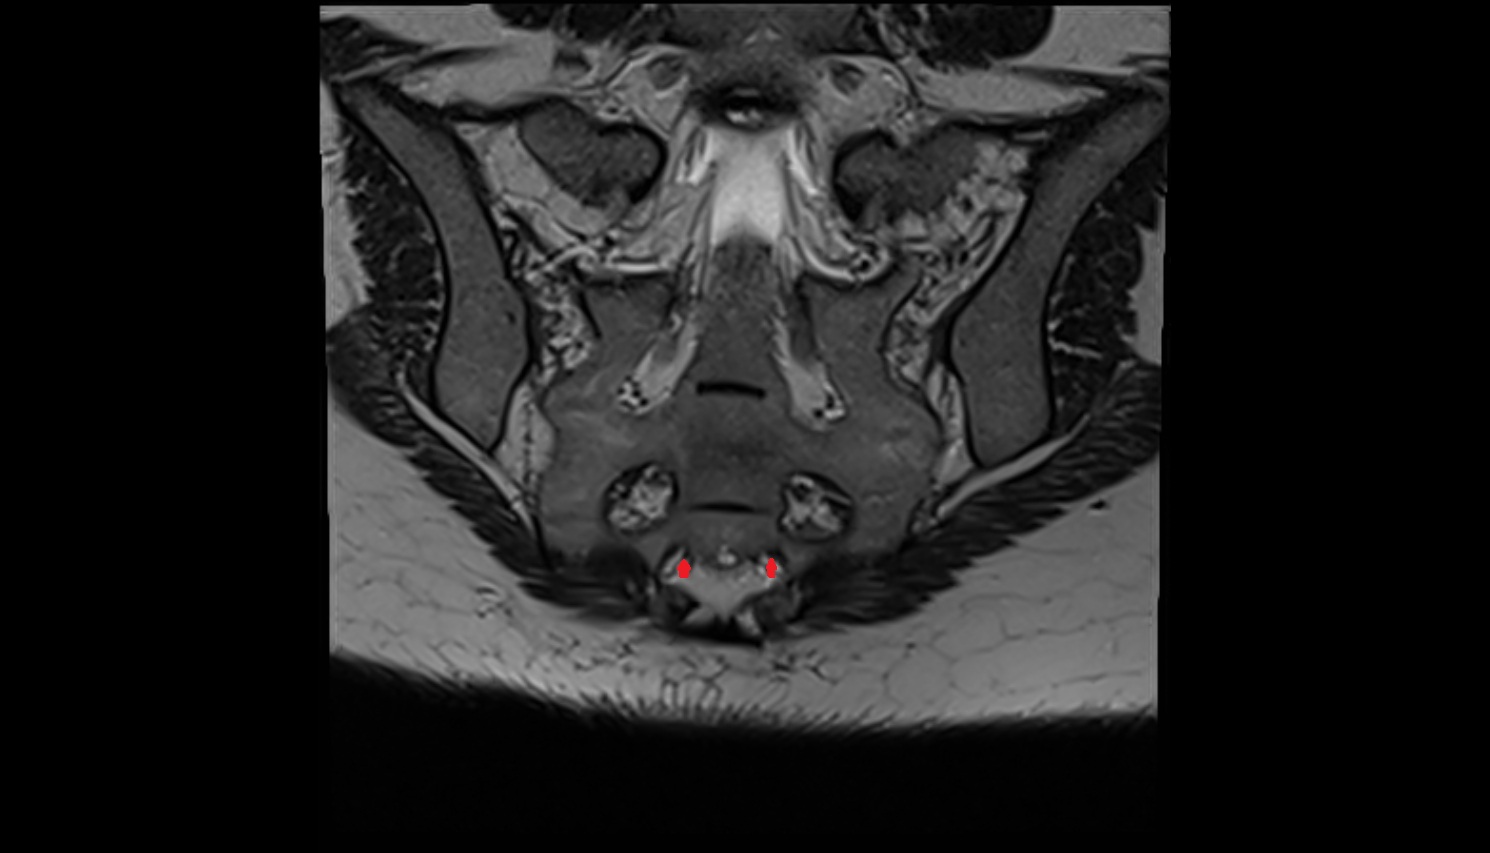

- Peripheral zone of prostate

- Anterior Fibromuscular Stroma of prostate

- Central zone of prostate

- Transitional zone of prostate